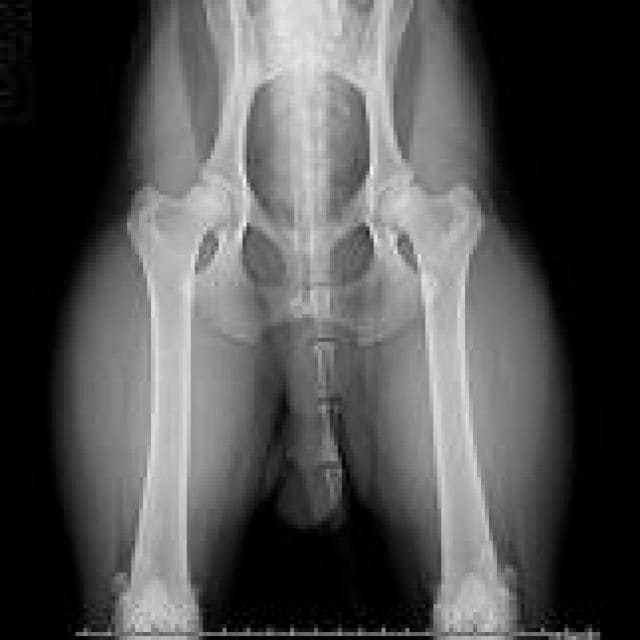

Golden Retriever Hip Dysplasia Surgery Cost. 2020-12-21 Hip dysplasia This is a form of arthritis in the joints of larger dogs such as Goldens. Corrective action with complications sometimes important.

As with any orthopedic surgery an infection can pose a serious threat to the recovery and usually antibiotics are prescribed during convalescence. Lack of proper nutrition in the dogs diet Delayed endochondral ossification Articular cartilage damage Synovial inflammation Golden Retriever Hip Dysplasia Signs How apparent the signs of hip dysplasia are in your dog will depend on four primary. 2020-04-21 The cost of treatment for hip dysplasia in dogs depends on the type of surgery that is undertaken. Corrective action with complications sometimes important.